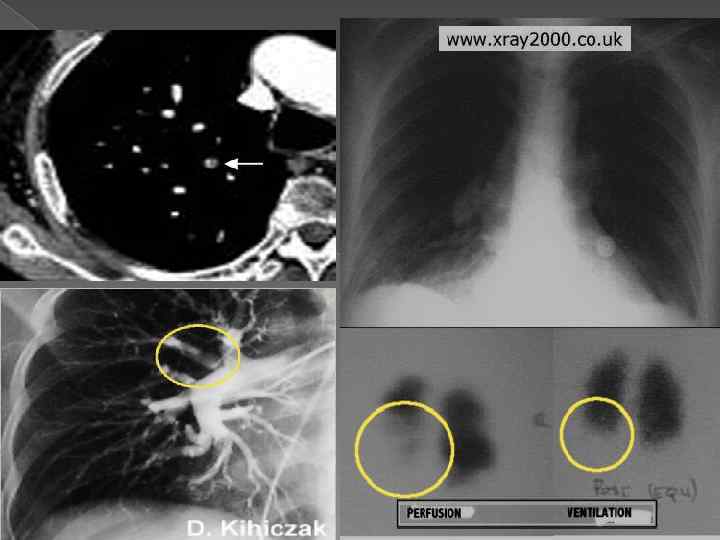

Диагностика Определение уровня d димеров «D димер» крови (уровень продуктов распада кровяных сгустков. Если тест показывает отрицательный результат, это указывает на то, что существует меньшая вероятность того, что человек имеет эмболию легочной артерии. В случае повышенного уровня тест менее полезен, так как известно, что многие состояния вызывают повышение данного уровня. В их числе такие состояния, как беременность, рак, недавно проведенные операции и инфекция). Инструментальные методы диагностики Рентгенологическое исследование грудной клетки помогает обнаружить небольшие изменения в структуре кровеносных сосудов после эмболии, позволяет выявить инфаркт легкого; впрочем, даже когда они заметны, поставить точный диагноз не всегда возможно. Электрокардиограмма (ЭКГ) выявляет изменения сосудов. Однако отклонения на ЭКГ бывают нестойкими и позволяют только заподозрить возможность эмболии легочной артерии. Перфузионная сцинтиграфия легких проводится следующим образом. Небольшое количество радионуклидного вещест ва, вводимого в вену, поступает к легким и позволяет оценить их кровоснабжение (перфузию). Области, где нормальное кровоснабжение отсутствует, выглядят на снимке темны ми, поскольку туда не попадают радионуклидные частицы.

Оценка вентиляции легких обычно проводится в сочетании с перфузионной сцинтиграфией. Человек вдыхает газ, содержащий небольшое количество радионуклидного вещества, которое распределяется в альвеолах легких. Области, где проис ходит обмен кислорода, видны на сканограмме. Сравнивая это изображение с изображением кровотока, полученным при оценке перфузии, врач определяет, имеется ли у пациента эмболия легочной артерии, так как в зоне закупорки вен тиляция может быть нормальной, а перфузия умень шенной. Венозная допплерометрия (ног, а иногда рук) может подтвердить наличие или отсутствие ТГВ. КТ ангиопульмонография. Такой метод не является 100% показателем при диагностике легочной эмболии, но по мере развития КТ, этот тест приближается к золотому стандарту ангиограммы. Легочная артериография наиболее точный метод ди аг ностики эмболии легочной артерии, однако она сопря жена с определенным риском и является более сложным иссле дованием. В артерию вводят контрастное вещество, которое попадает в артерии легких. На рентгеновском снимке эмболия легочной артерии выглядит как закупорка в артерии.